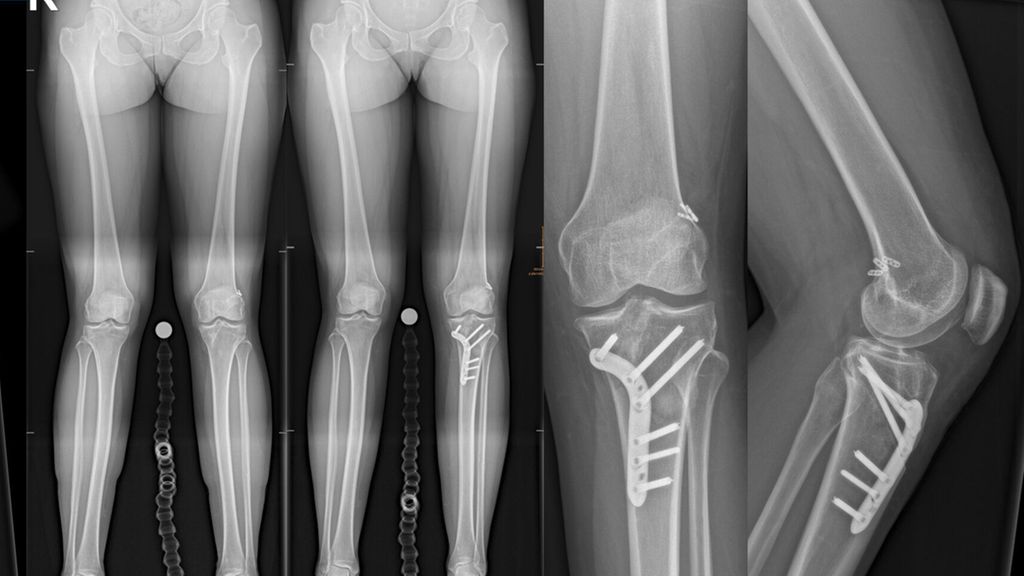

Abb. 2: 33-jährige ehemalige Leichtathletin mit einer primären VKB-Ruptur (A), deutliche Chondropathie im medialen Kompartiment, Varusfehlstellung von 9° primär aus dem distalen Femur resultierend (LDFA 92° [C]), behandelt mit einer einzeitigen CW-DFO und VKB-Plastik (4-Strang-Semitendinosus-Graft)